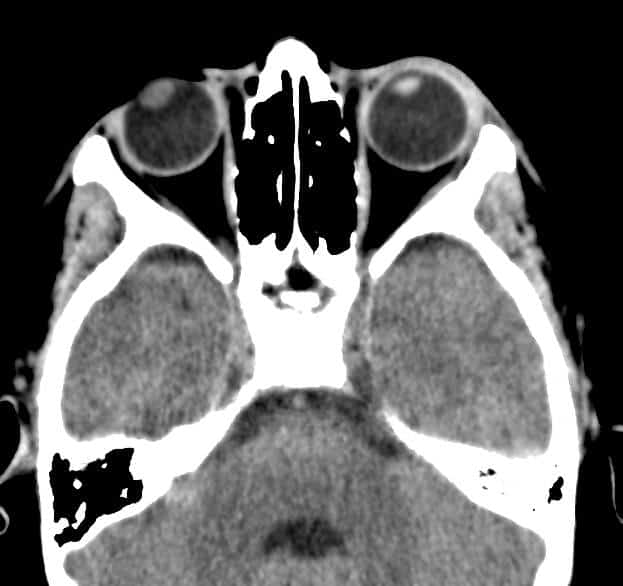

Đục thủy tinh thể trái

Chấn thương nhãn cầu

» Thông tin: Nam giới – 10 tuổi.

» Lâm sàng: Mù mắt phải sau chấn thương.

# Thủy tinh thể phải giảm tỷ trọng do phù nề.